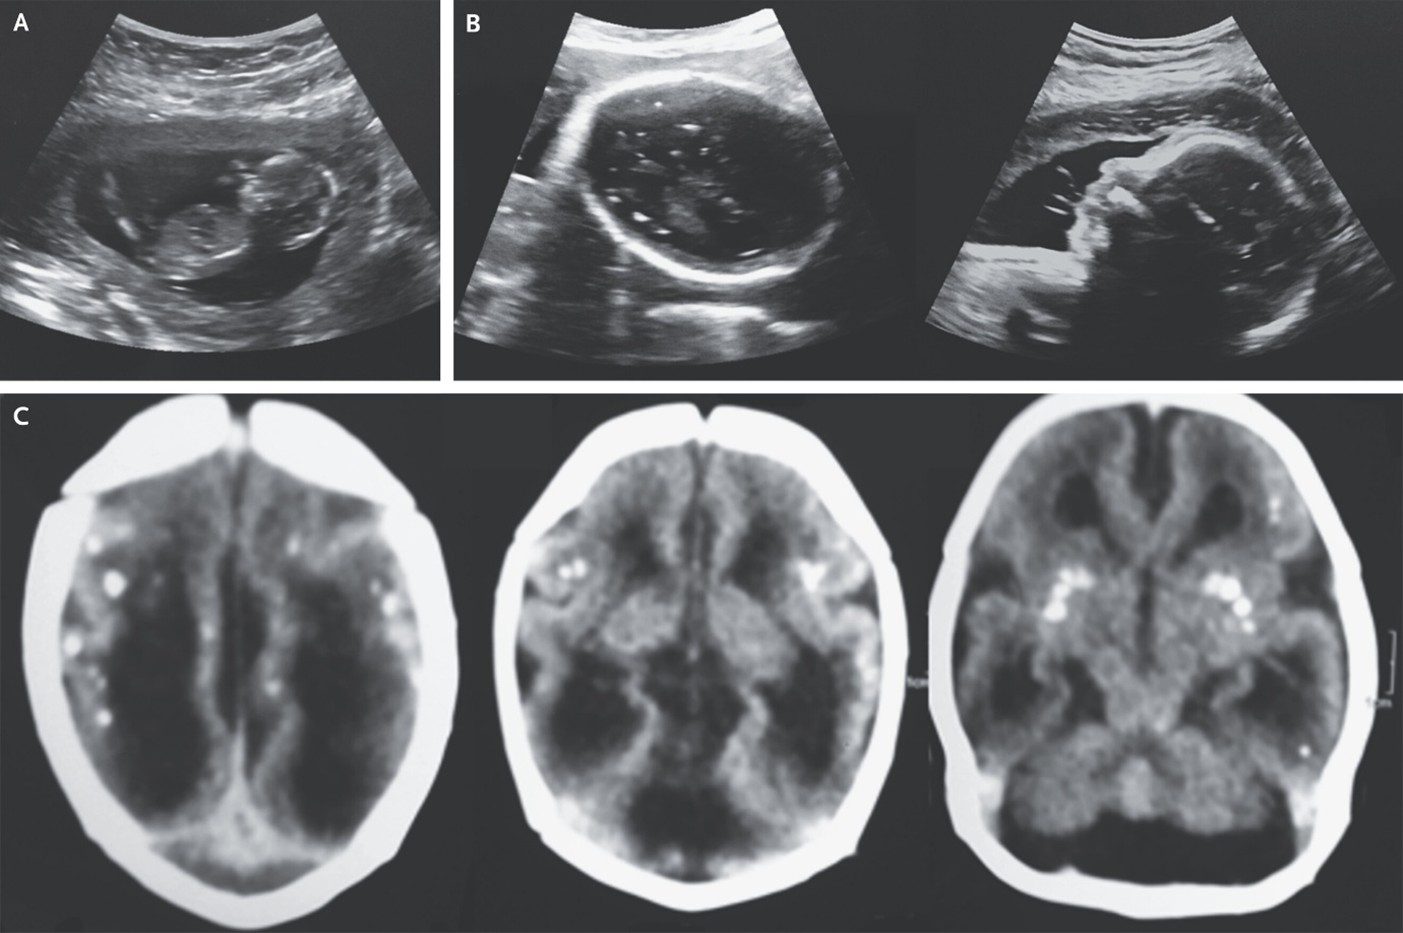

(3) Congenital Zika Syndrome

Felipe Baccin et al, published December 29, 2025, New Engl J Med 2026;394: e2, DOI: 10.1056/NEJMicm2511220, VOL. 394 NO. 1

A 6-month-old boy was referred to a pediatric neurology clinic in Brazil for evaluation of developmental delay. CT of the head at 1 month of age had shown lissencephaly and intracranial calcifications.